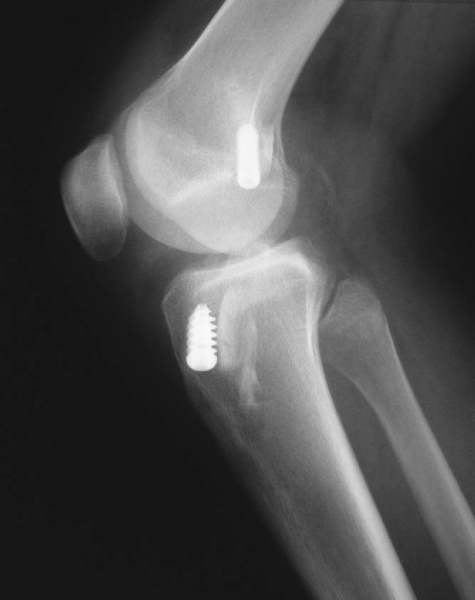

Errors in surgical technique, especially with tunnel positioning, are considered the most common causes of recurrent instability. The typical mistakes seen with tunnel malpositioning have evolved during the early years. The early two-incision arthroscopic procedures were commonly associated with anteriorly placed femoral or tibial tunnels (

Fig. 64-1

); the single-incision endoscopic technique, at least in its early years, was associated mainly with anteriorly placed femoral tunnels. During the past 5 years, the most common patterns of tunnel malpositioning have been a combination of vertically oriented femoral tunnels and posteriorly positioned tibial tunnels (

Fig. 64-2

). Although commercially available femoral aiming devices have resulted in more accurately positioned femoral tunnels in the anteroposterior plane, these tools do not protect against a vertical orientation, which does not adequately restore rotational stability. On clinical examination, patients may demonstrate a normal Lachman test result but have a demonstrable pivot shift phenomenon. This problem of improper femoral tunnel position has led some surgeons to contend either that primary ACL surgery should be performed with a two-incision technique or, more recently, that double-bundle femoral and tibial tunnels be used.